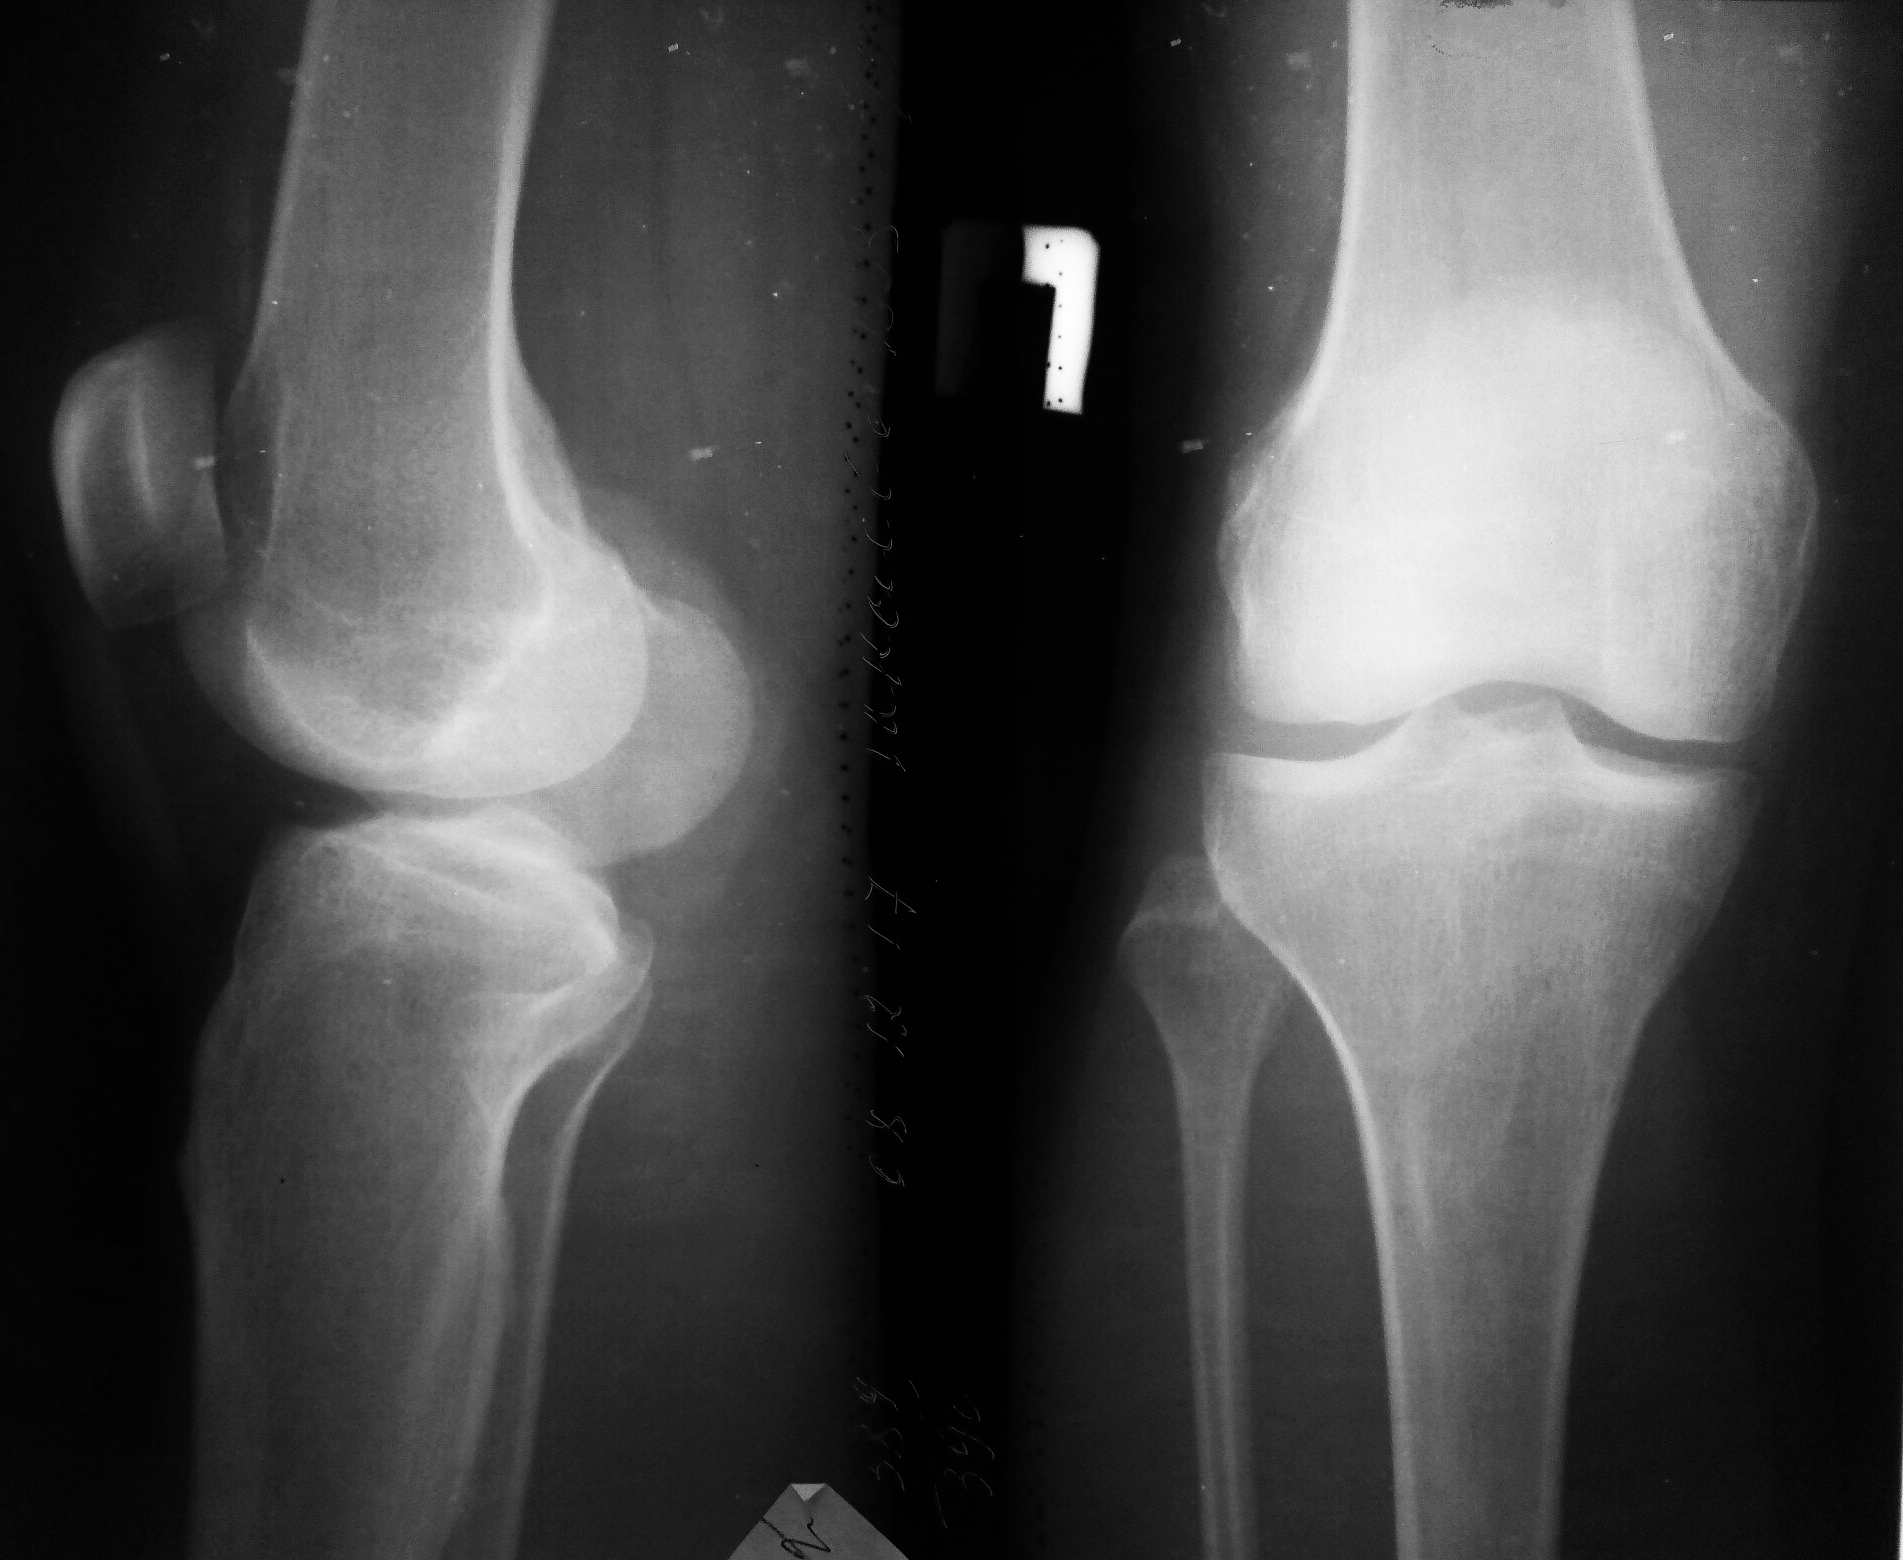

Фото и диагностика кисты Бейкера